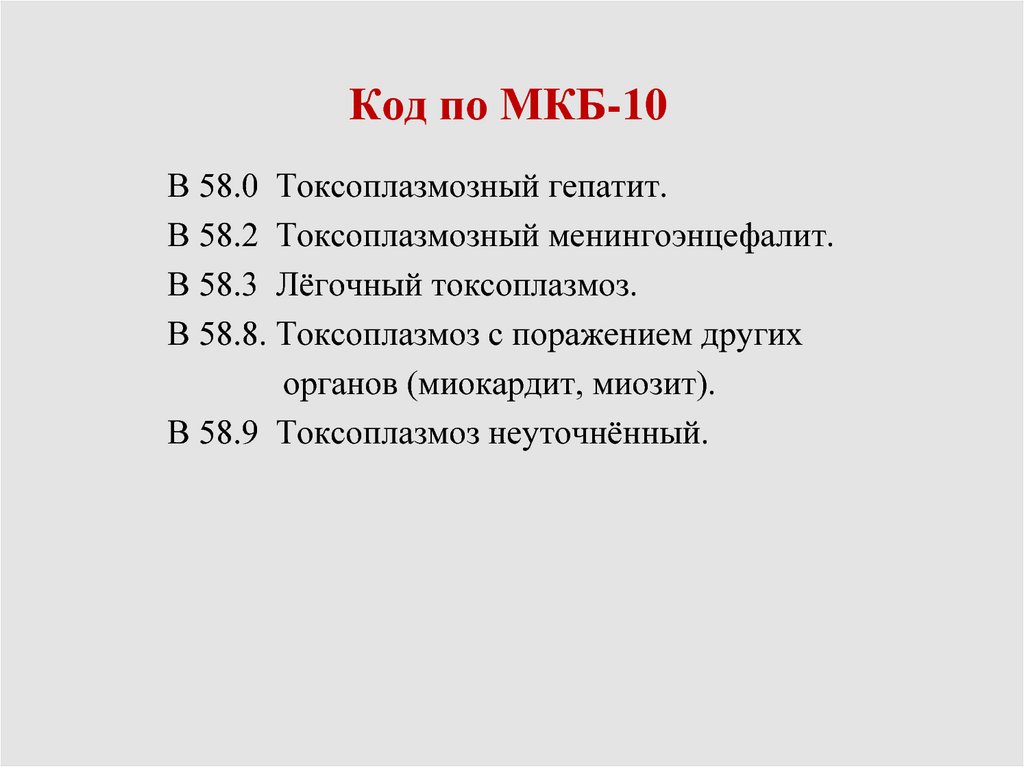

Код мкб 10 атерома головы

Код мкб 10 атерома головы 109 фото